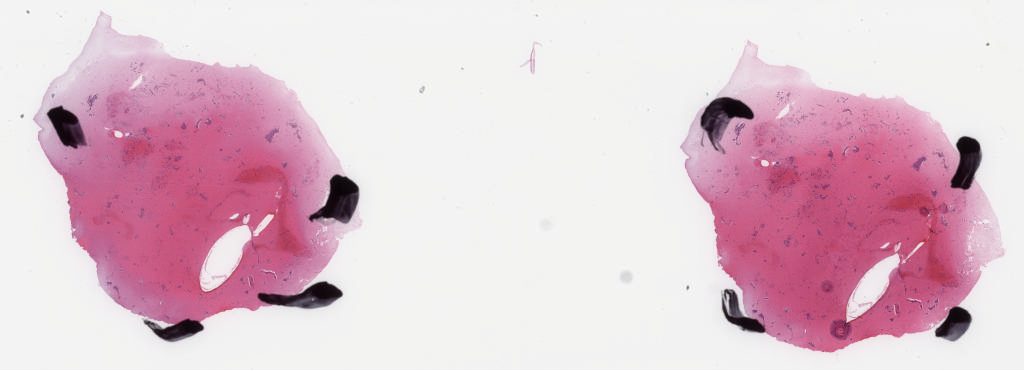

1791949.svs

137447

x

49791

@

40X